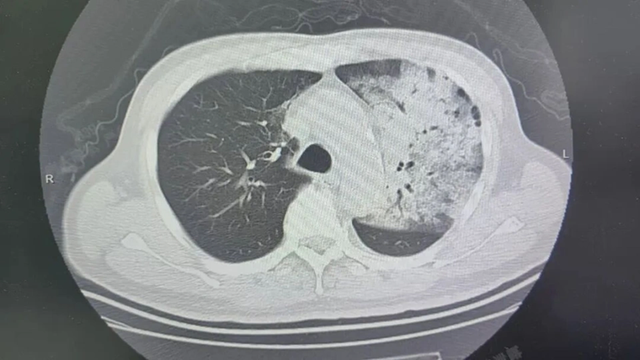

Sau khoảng một tuần điều trị tại bệnh viện địa phương, bệnh tình của ông đột ngột xấu đi. Bệnh nhân bắt đầu khó thở, rối loạn ý thức. Kết quả chụp CT cho thấy 2 phổi bị nhiễm trùng nặng, gần như “trắng xóa”. Dù đã được hỗ trợ thở máy nhưng tình trạng oxy máu vẫn không cải thiện.

Người đàn ông sốt 40 độ C, phổi gần như “trắng xóa”, chỉ vài ngày đã suy đa tạng: Thủ phạm liên quan đến thói quen nhiều gia đình vẫn mắc - Ảnh 1.